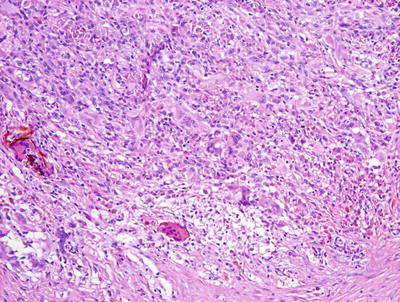

Nonallergic foreign body granulomas demonstrate an admixture of lymphocytes, histiocytes, multinucleated giant cells and, in early lesions, clusters of neutrophils [2, 3] (Fig. 6.1). The most common foreign material that elicits this type of reaction within the skin is keratin , often secondary to a ruptured folliculitis. The keratin is often readily identified within multinucleated giant cells. Other materials may be similarly located and can be visualized with routine microscopy or in some cases highlighted with light polarization (Fig. 6.2). Foci of necrosis are often seen centrally and surrounded by the granulomatous reaction. Changes within the overlying epidermis are related to route of entry of the foreign material into the dermis , and may display ulceration or epidermal acanthosis if the material has been present for a period of time and caused secondary local trauma from rubbing.

Fig. 6.1

A dense granulomatous infiltrate characterized by multinucleated giant cells and a mixed inflammatory infiltrate is seen in foreign body type granulomas. Foreign material can be apparent on routine H&E sections